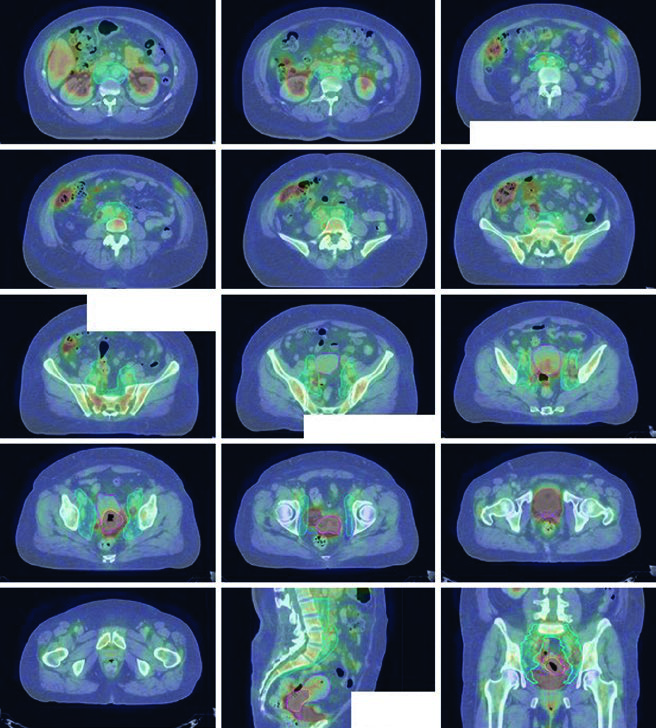

A fusão do PET/CT pré-tratamento com a TC de simulação é recomendada para auxiliar no delineamento do volume tumoral bruto (GTV). Diretrizes internacionais de consenso para contorno em casos de cérvice definitiva já foram publicadas, e casos-amostra interativos estão disponíveis em plataformas educacionais como o eContour.

A IMRT demonstrou reduzir toxicidade GI e hematológica, e pode melhorar toxicidade urinária relatada pela paciente. O PET/CT pode ser usado para segmentar sub-regiões ativas de medula óssea, onde acúmulo de dose correlaciona-se com maiores taxas de toxicidade hematológica. Poupar medula metabolicamente ativa com IMRT reduziu neutropenia e melhorou tolerância à quimioterapia em ensaios clínicos prospectivos.